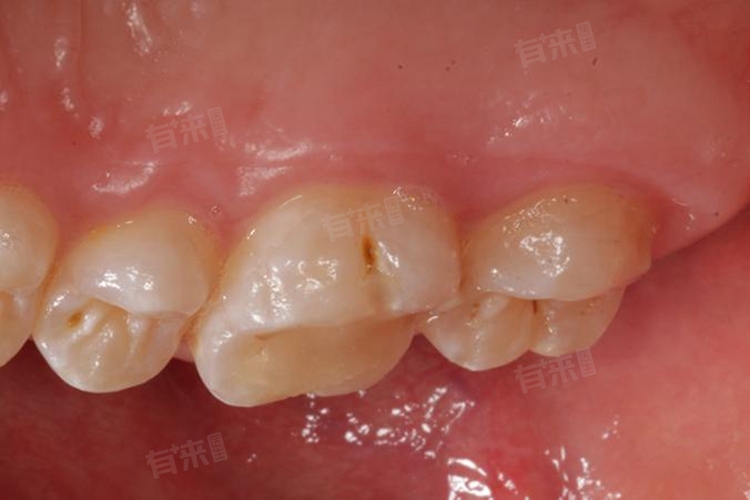

1、龋齿:龋齿是最为常见的导致“烂牙”的原因,也就是我们俗称的蛀牙。从本质上来说,它是一种细菌性疾病。口腔中的细菌,如变形链球菌、乳酸杆菌等,会与食物中的糖分相互作用,产生酸性物质。这些酸性物质会逐渐腐蚀牙齿表面的牙釉质,使牙釉质脱矿,进而形成龋洞。一开始,龋洞可能只是牙齿表面一个小小的黑斑或白垩色斑块,随着时间推移,龋洞会不断加深,侵蚀牙本质,甚至到达牙髓腔。当龋洞发展到一定程度,牙齿就会出现明显的缺损,看起来就像“烂掉”了。

另外,还可能是指残根残冠。当龋齿或牙髓坏死等疾病没有得到及时有效的治疗,牙齿会不断被破坏。严重时,牙齿大部分结构被侵蚀,只剩下残留的牙根和部分牙冠,这就是残根残冠。残根残冠不仅影响美观,还容易成为细菌滋生的温床。由于其表面不平整,刷牙等口腔清洁措施难以彻底清除细菌和食物残渣,细菌在上面大量繁殖,会持续破坏剩余的牙齿组织,使“烂牙”的情况愈发严重。